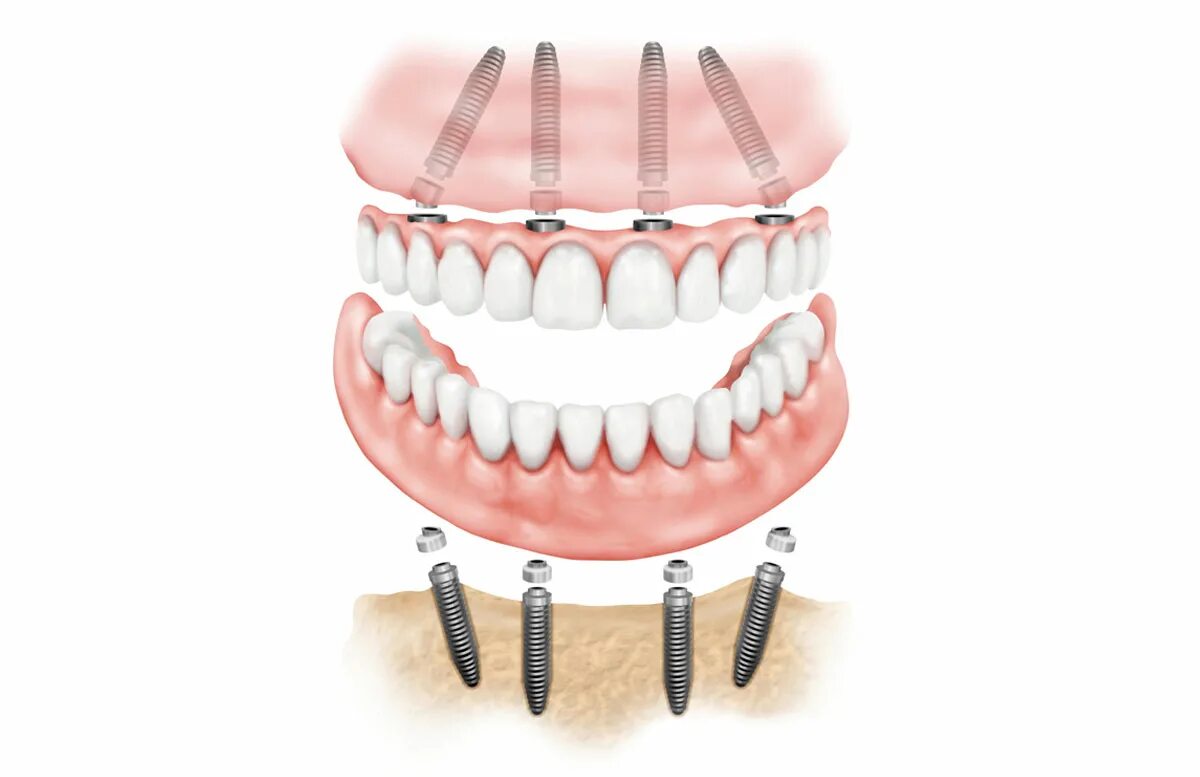

Поставить 4 зуба